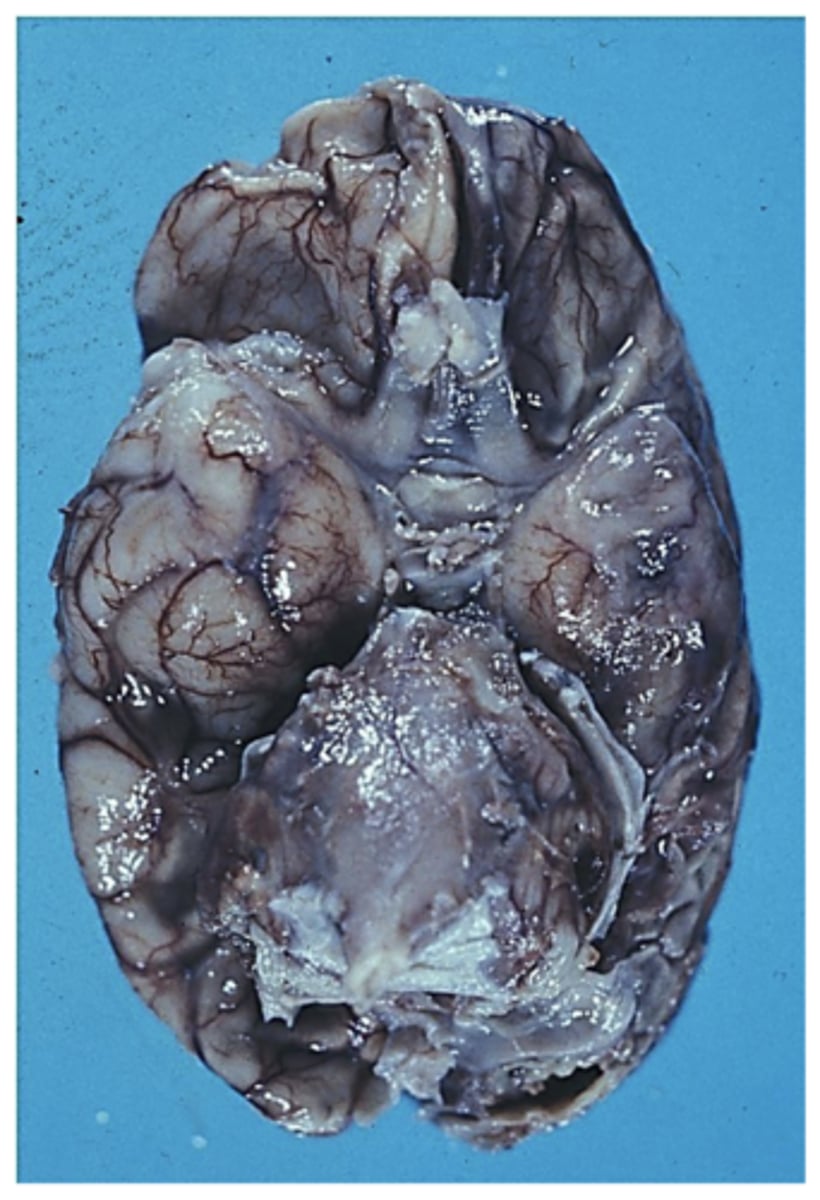

greyish, gelatinous, viscous exudate covers the base of the brain

What happens in tuberculosis meningitis, a form of CNS tuberculosis?